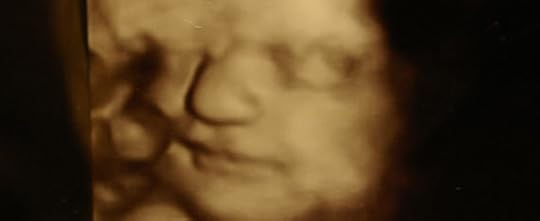

Another powerful tool to teach children about the value of the unborn is intrauterine pictures (such as these) and ultrasound photographs. In years past, the biggest disadvantage to the preborn child has always been that there’s no window to the womb. But in recent years this has radically changed.

Expecting parents often share ultrasound pictures and video on social media. As you view these with your children, you can talk about how precious and fully human the babies are, and what a miracle that we are “fearfully and wonderfully made” (Psalm 139:14).